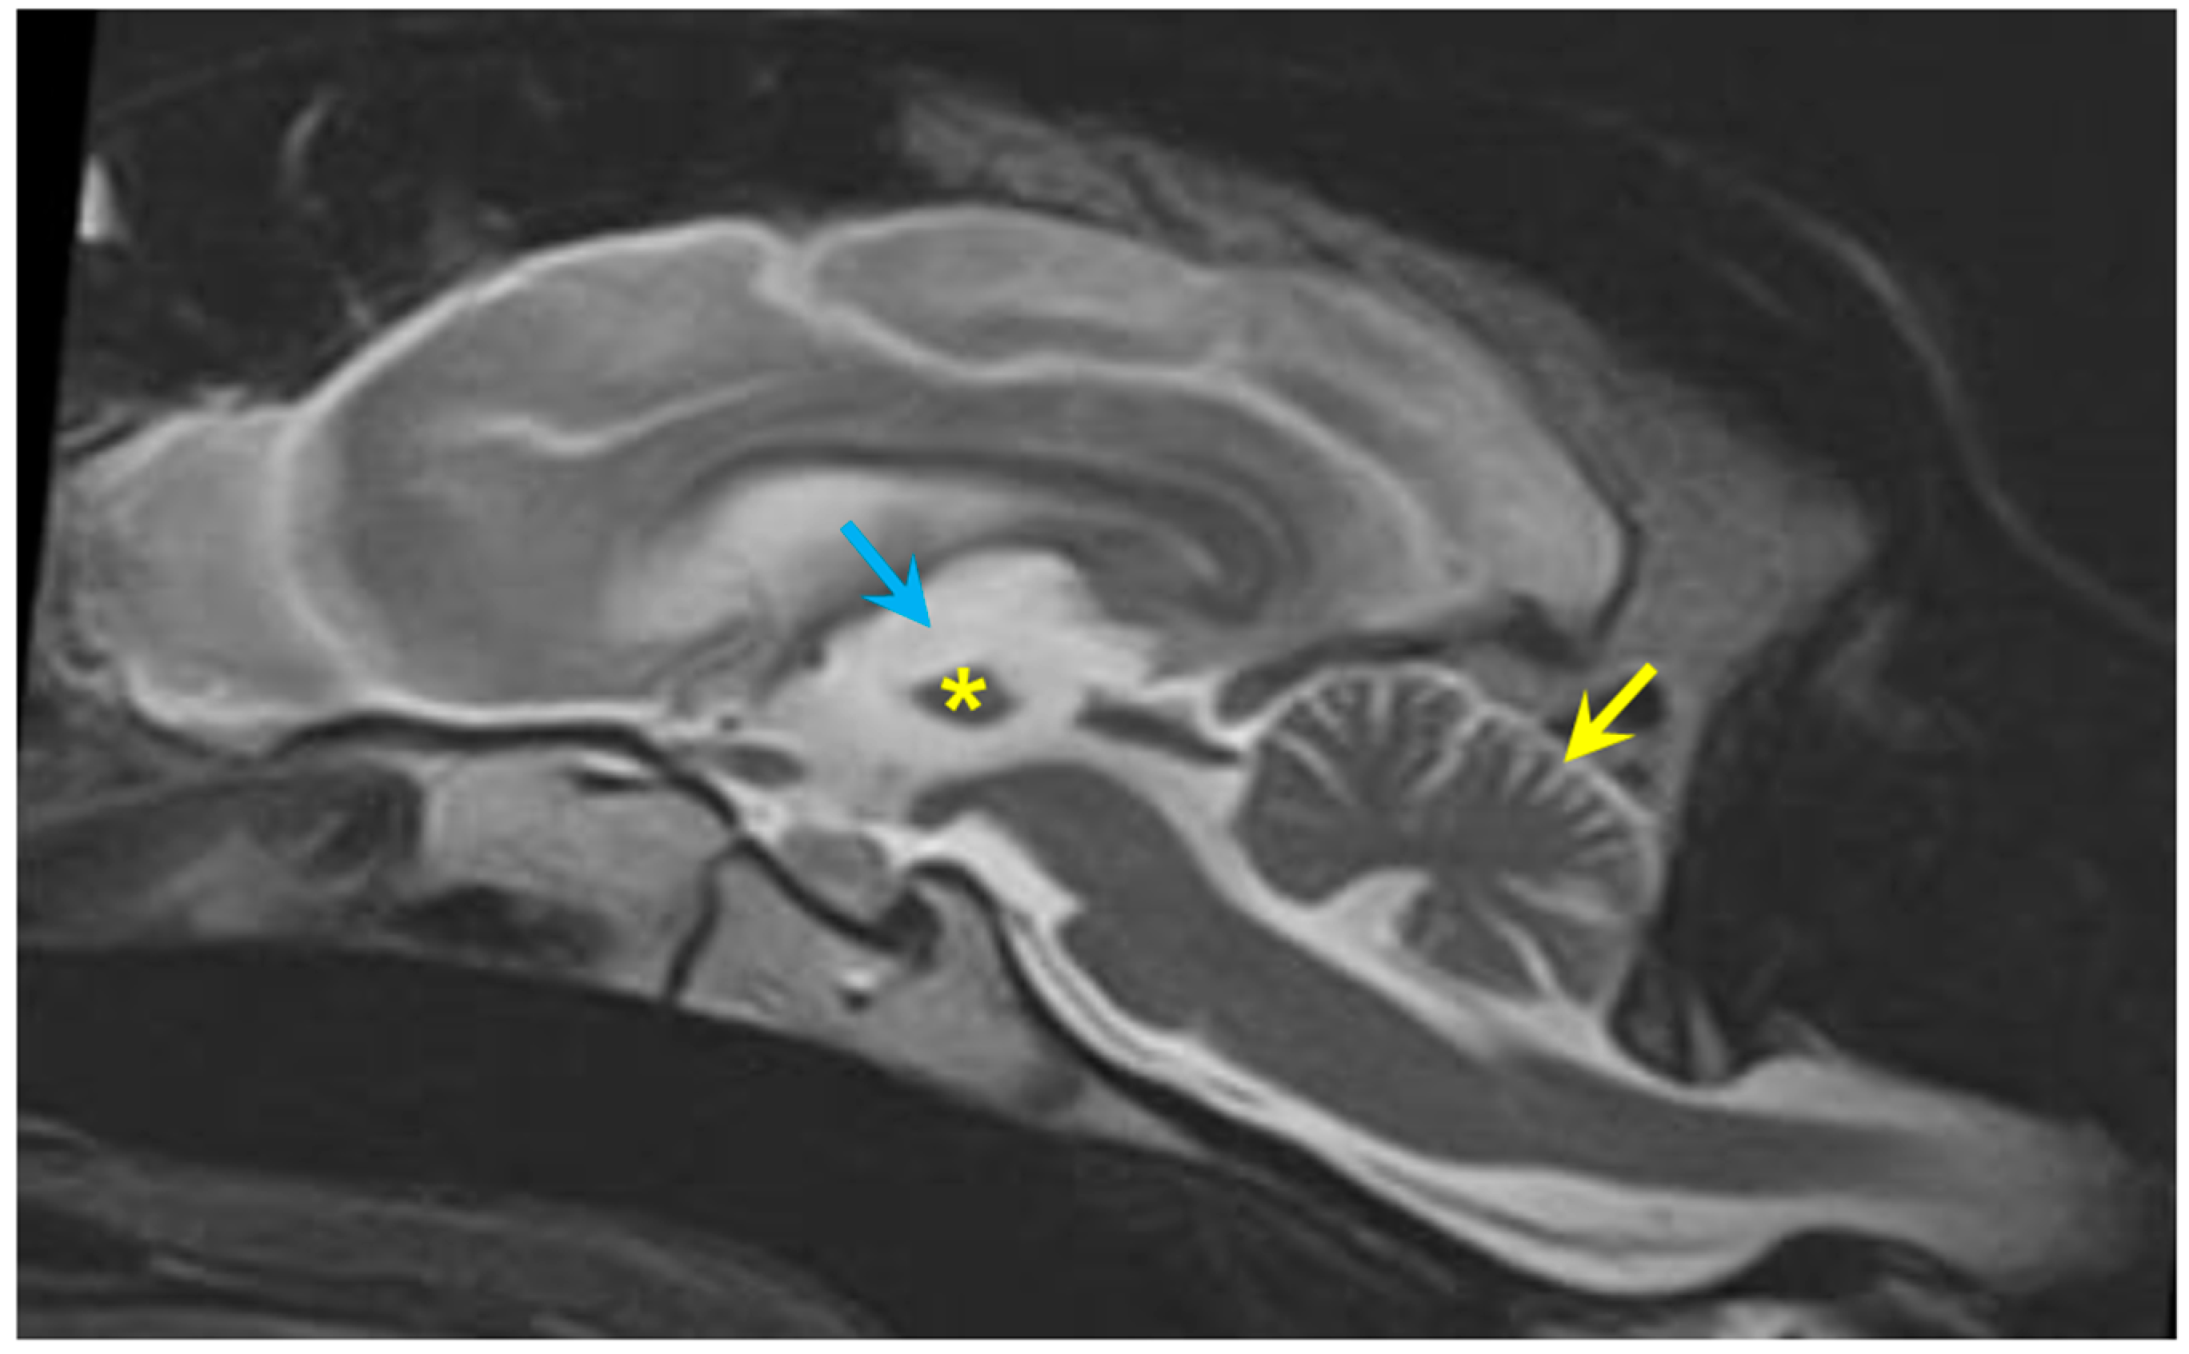

3.1. Disease Phenotype

3.2. Microscopic Findings